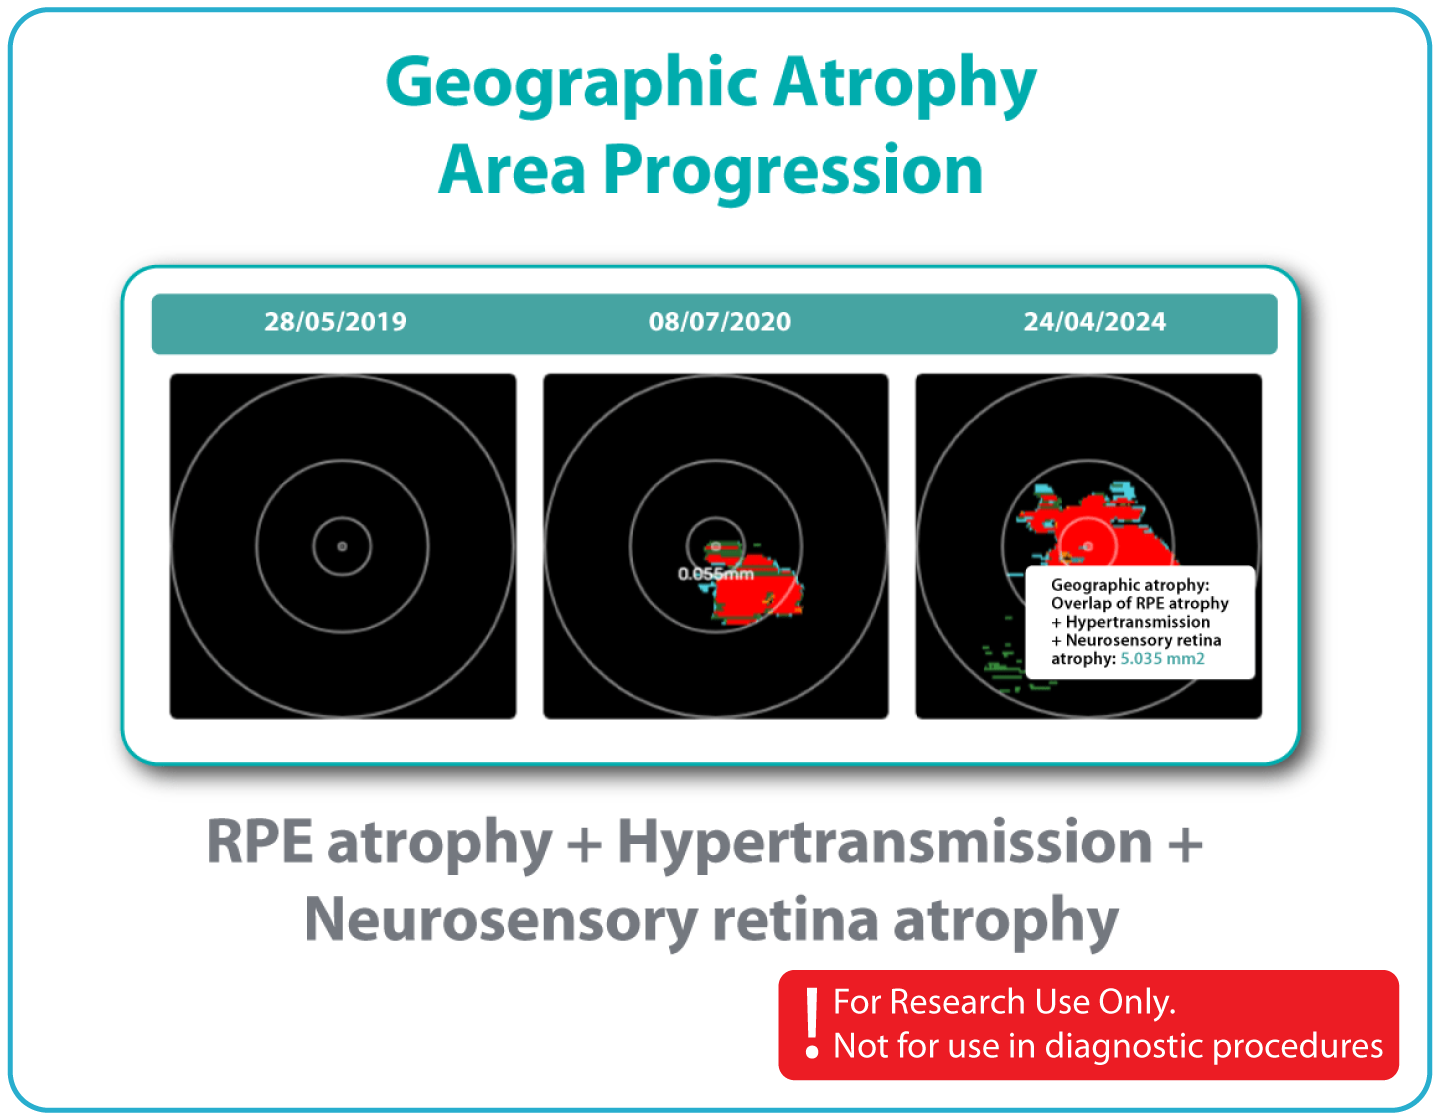

Longitudinal review of feature changes across multiple examinations, expressed in linear or percentage-based measurements.

The GA Progression feature provides tools for research-oriented visualization and comparison of OCT imaging data across multiple visits. Users can review changes in areas associated with geographic atrophy (GA) and related imaging features through percentage-based displays, maps, and graphs.

Efficient estimations of GA-associated areas designed to support research-focused image review workflows.

Quantitative, image-derived measurements of GA-related features and associated biomarkers for research analyses.